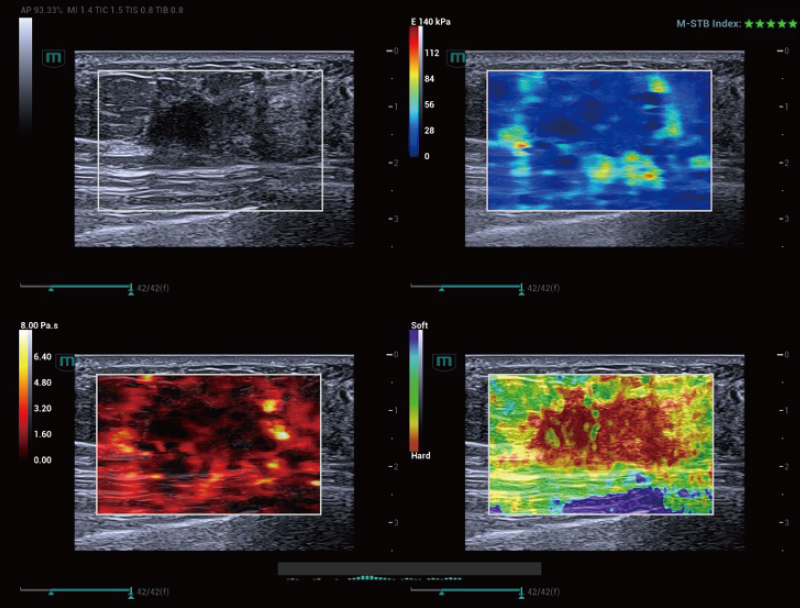

STVi consente la valutazione quantitativa della viscosit├Ā dei tessuti e fornisce immagini multiparametriche in tempo reale, offrendo un approccio pi├╣ completo alla diagnosi per immagini e all'analisi quantitativa di malattie epatiche croniche, lesioni mammarie e altre condizioni.

Coefficienti quantitativi doppi

Valutazione della malattia epatica cronica

Strumenti di quantificazione multipli

Valutazione del tumore al seno